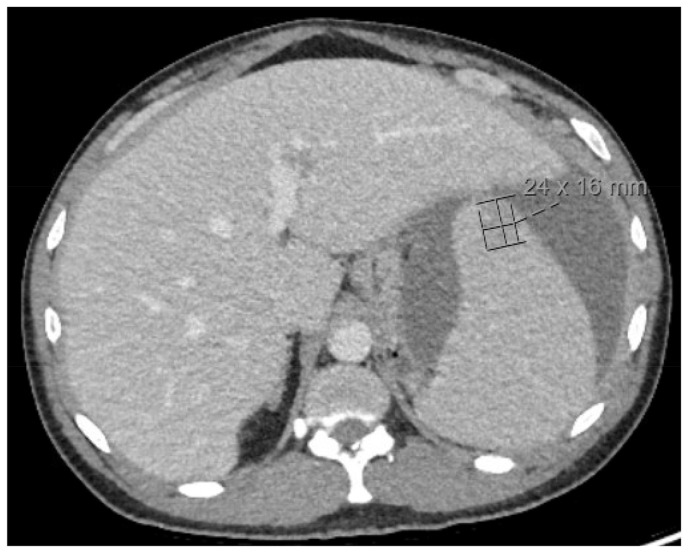

Case presentation: A 42-year-old man presented with persistent left upper quadrant pain radiating to the lower quadrants ongoing for many months. He additionally had many other systemic symptoms including weight loss, night sweats, dark tarry stools, and progressive fatigue. Initial laboratory tests showed an anemia and a leukocytosis of 170 K/mm3 which uptrended to 230 K/mm3. CT abdomen showed spontaneous splenic rupture without major hemodynamic compromise and was treated conservatively. Peripheral smear was indicative of a chronic leukemia, and BCR-ABL testing was positive, leading to the diagnosis of CML - a rare cause of SSR.